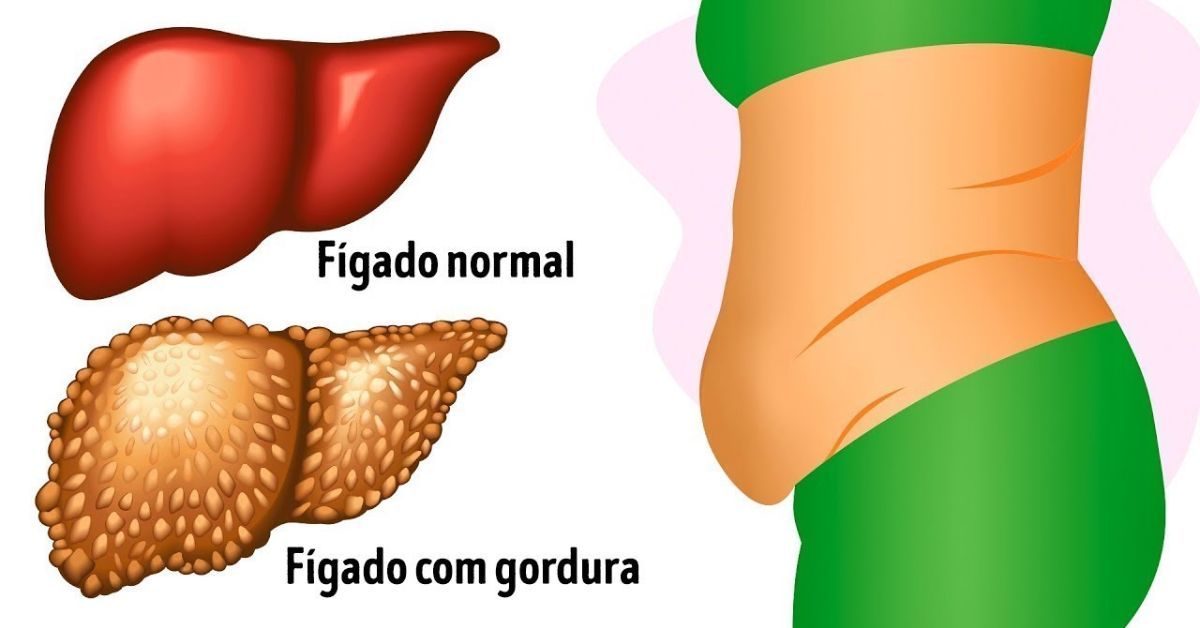

A esteatose hepática, também conhecida como gordura no fígado, é uma condição frequente que impacta milhões de indivíduos globalmente. Em fases iniciais, essa condição pode não exibir sintomas evidentes, o que complica o diagnóstico antecipado. Contudo, à medida que a enfermidade avança, pode resultar em complicações mais sérias, como a esteato-hepatite não alcoólica (NASH), cirrose e até mesmo câncer hepático.

Essas complicações surgem quando a inflamação e a lesão do fígado progridem, afetando significativamente a sua funcionalidade e a saúde geral do paciente. No entanto, na fase inicial, tudo pode ser revertido: para diminuir a gordura no fígado, normalmente é necessário perder de 5% a 7% do peso corporal.

A perda de peso deve ser acompanhada de mudanças no estilo de vida, como a adoção de uma alimentação saudável e balanceada, rica em fibras e pobre em gorduras saturadas e açúcares, além da prática regular de exercícios físicos. A moderação no consumo de álcool e a eliminação de hábitos prejudiciais, como o tabagismo, também são essenciais para a melhora da saúde hepática.